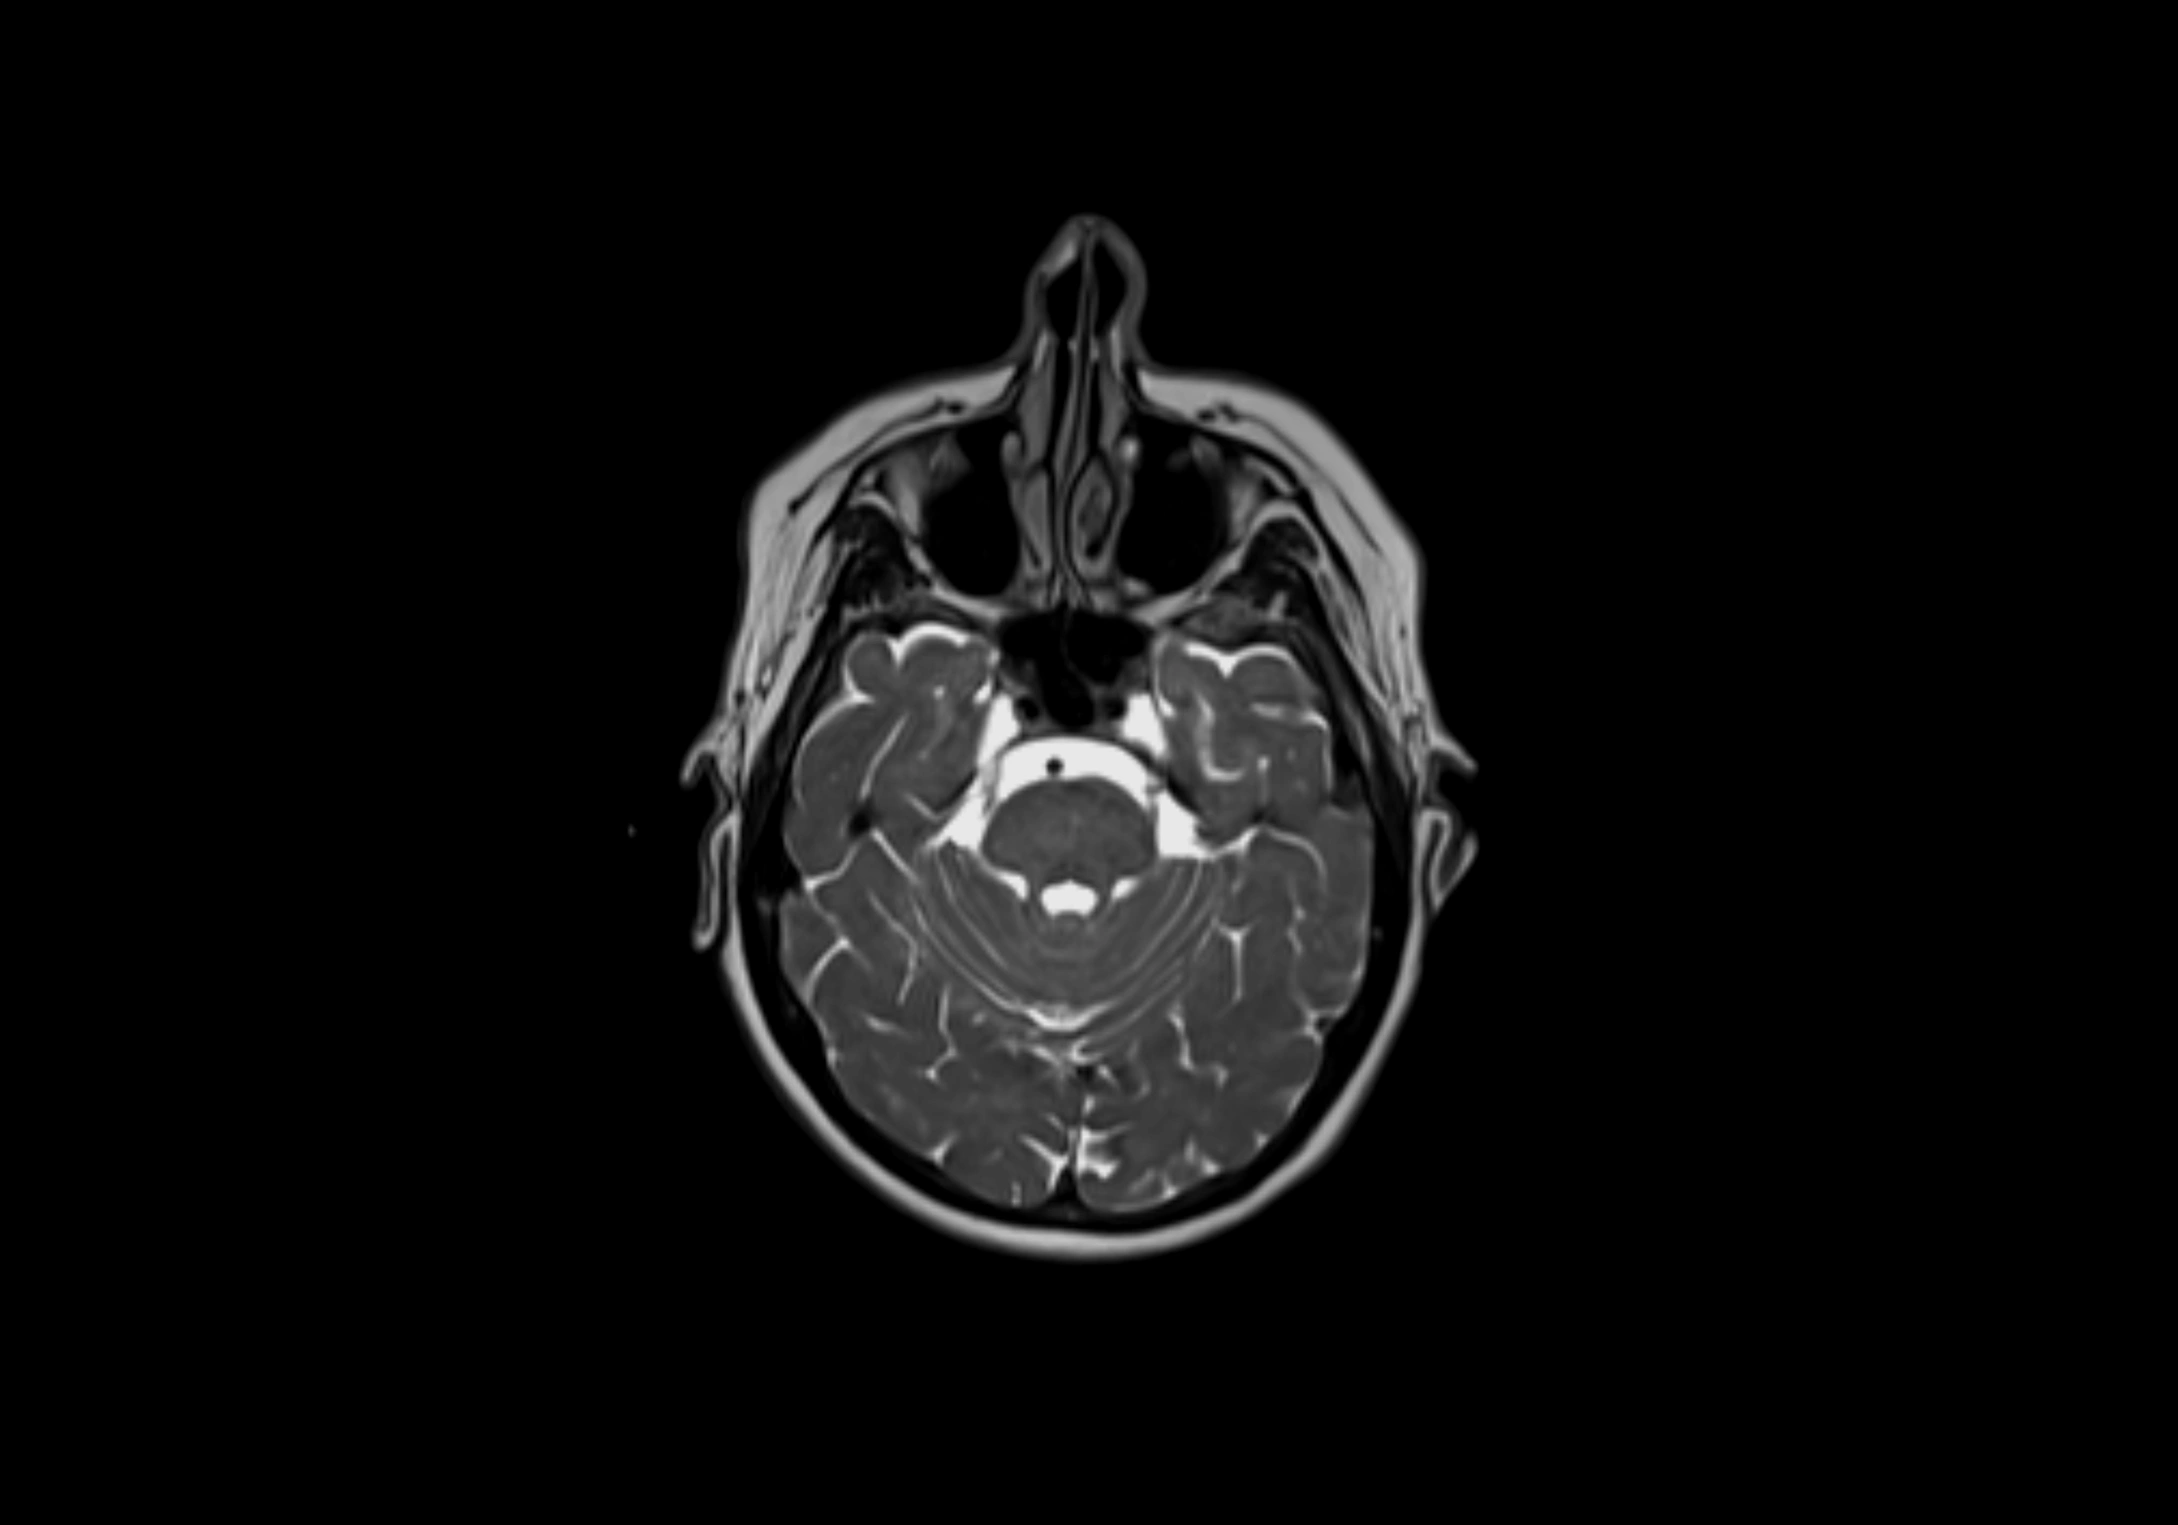

MRI Appearance

T2-weighted images:

• Nodes show intermediate signal, with surrounding fat bright

• Useful for detecting edema, inflammation, or infiltration

• Fatty hilum may appear slightly hyperintense relative to cortex

MRI images

image